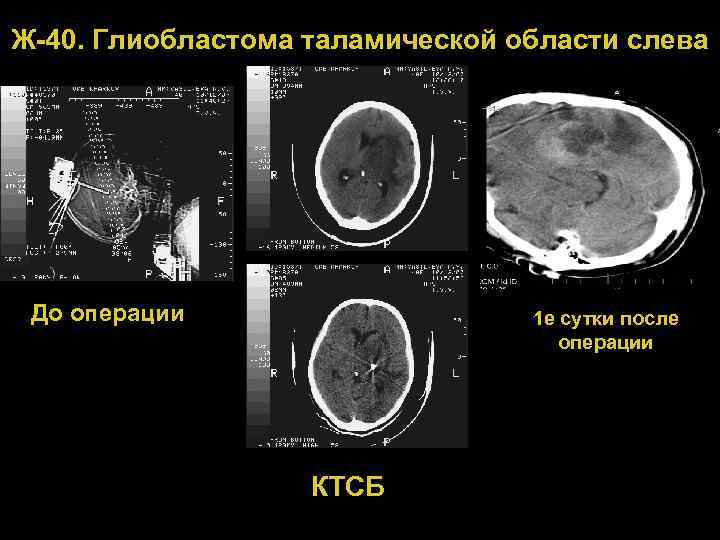

Ж 40. Глиобластома таламической области слева До операции 1 е сутки после операции КТСБ 72

М-54. Глиобластома таламической области слева До операции КТСБ, осложненная кровоизлиянием После дренирования 73 гематомы

М 54. Глиобластома таламической области слева СКТ, 6 е сутки после операции МРТ до операции МРТ, 5 месяцев после операции и лучевой терапии 74